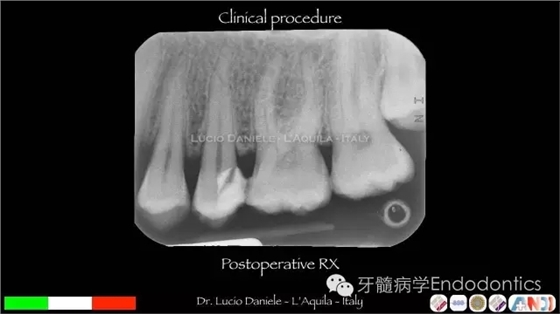

圖19.臨床操作

圖24.術后X線片